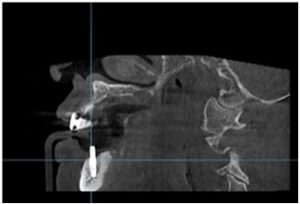

양산수면치과 에이디중부치과에서는

임플란트 식립을 진행하기 전

파노라마 사진과 3D CT 사진 촬영을 통해

위턱의 경우 상악동과의 거리,

아래턱 하방으로 지나가는

하치조 신경관의 위치,

잔존 치조골의 양과 두께,

눈에 보이지 않는 해부학적 구조물 등을

면밀하게 확인하는 과정을 거쳤으며,

이러한 결과를 토대로

임플란트를 식립하기 좋은 위치를 선정하고

식립 될 Fixture의 굵기와 길이,

식립 방향 등을

컴퓨터 분석과 시뮬레이션을 통해

미리 파악하는 과정을 거쳤는데요.